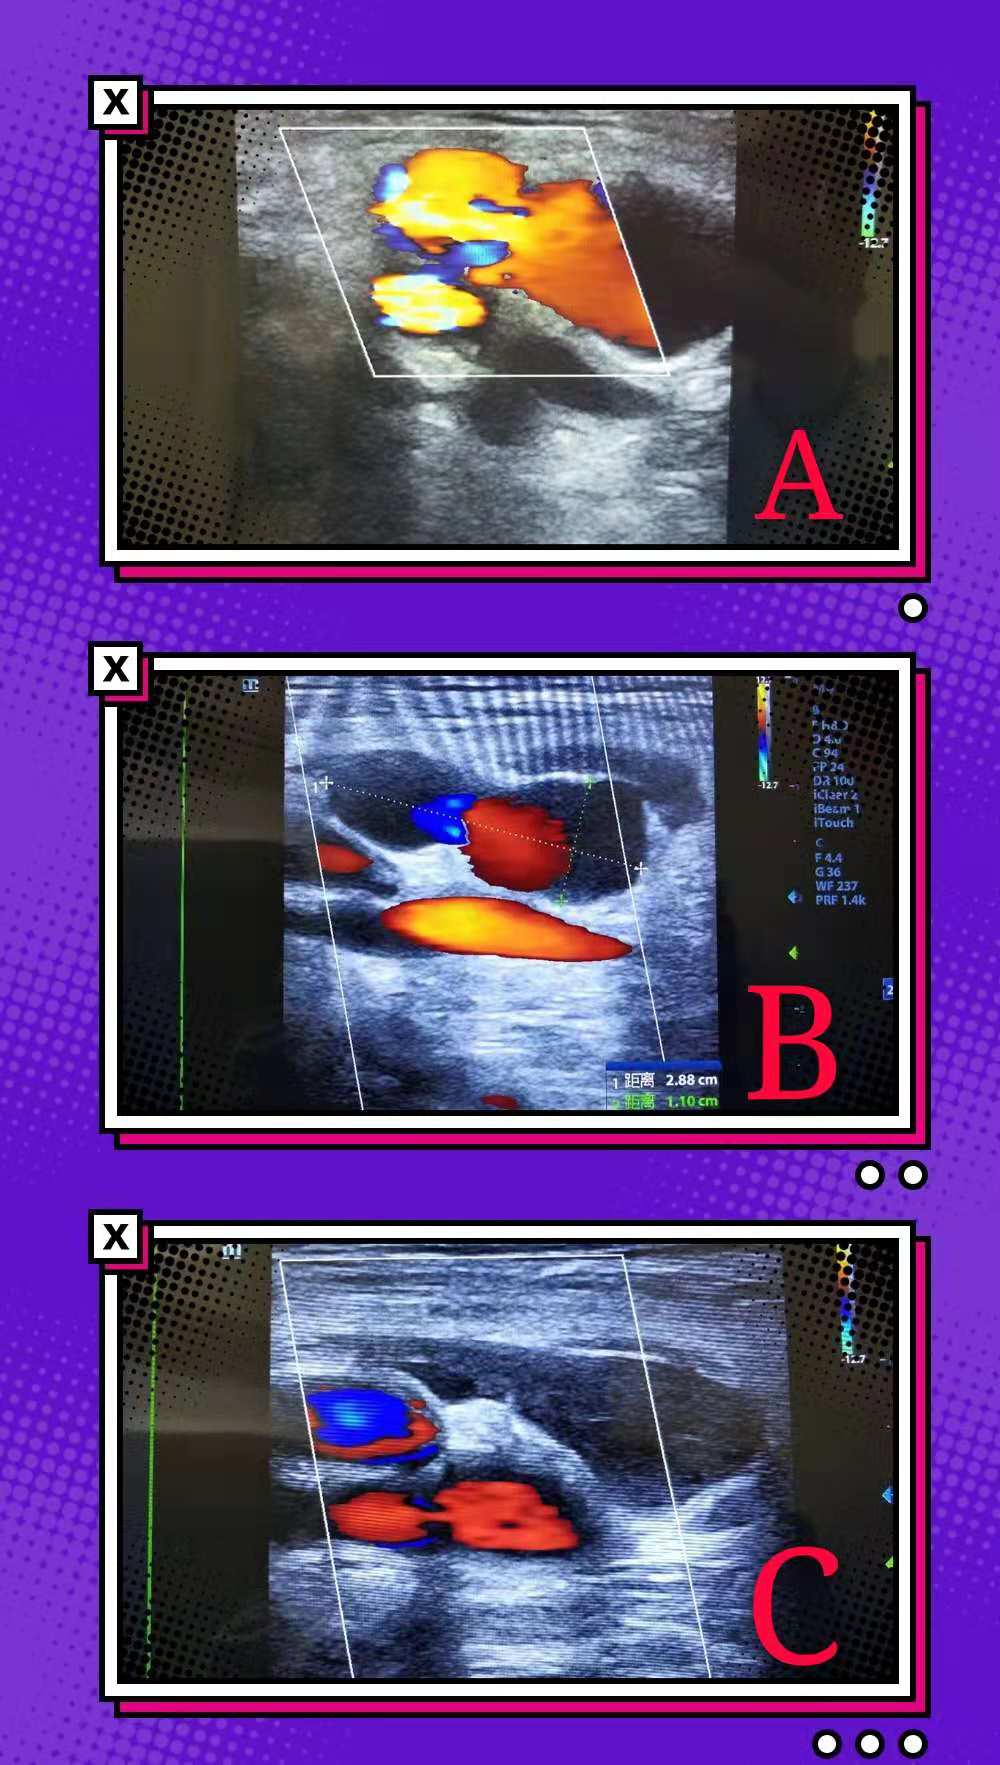

患者李女士, 因双侧下肢动脉血栓病,在中心医院神经内科进行血管扩张术,在术后出现双侧股总动脉假性动脉瘤,经过1天的局部加压包扎后仍未好转,经神经内科医师联合超声科的刘晓晖主任医师、韩婷婷医师商讨后决定为患者行超声引导下经皮假性动脉瘤凝血酶注射治疗术。术中耗费时间仅仅为10分钟。治疗完毕后局部压迫12小时后复查已经完全漏口已经完全闭塞,且患者术前术后生命体征平稳。

随着血管侵入技术的广泛开展,医源性假性动脉瘤的检出率为上升趋势。超声引导下注射凝血酶栓塞治疗假性动脉瘤因其成功率高且并发症发生率极低被广泛应用于临床。其优点主要有:1.成功率高;2.痛苦小,患者容易耐受;3.操作时间短;4.恢复快,复发率极低。对于导管术后采用全身抗凝治疗的患者,栓塞疗法要比加压疗法的成功率高而复发率低。